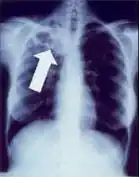

El foco de Ghon es un área inflamatoria pequeña en el parénquima pulmonar de naturaleza granulomatosa,debida a una resistencia ante la tuberculosis.[1] que solo puede ser detectable en una radiografía del tórax cuando se calcifica o si crece considerablemente. Por lo general estos focos inflamatorios se curan, pero en ciertos casos, en especial en pacientes inmunosuprimidos, progresará hasta desarrollar una tuberculosis miliar—llamados así por su apariencia en la radiografía a las semillas de mijo.

La ubicación clásica del foco de Ghon es en la vecindad o rodeando las fisuras del lóbulo superior de uno de los pulmones. Si el foco inflamatorio se extiende por multiplicación bacteriana, típicamente en las semanas 4-6 seguidas de la infección inicial, causando diseminación a los ganglios lnfáticos circunvecinos—en particular los ganglios paratraqueales donde drenan los lóbulos superiores—recibe el nombre de complejo de Ghon o complejo primario.[1] El foco de Ghon puede diseminar bacterias hacia el espacio pleural causando pleuritis.